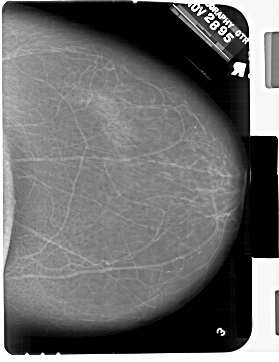

A_1332_1.LEFT_CC

LEFT_CC LINES 6871 PIXELS_PER_LINE 4951 BITS_PER_PIXEL 12 RESOLUTION 43.5 OVERLAY

FILE: A_1332_1.LEFT_CC.OVERLAY

TOTAL_ABNORMALITIES 1

ABNORMALITY 1

LESION_TYPE CALCIFICATION TYPE PLEOMORPHIC DISTRIBUTION CLUSTERED

ASSESSMENT 4

SUBTLETY 2

PATHOLOGY BENIGN

TOTAL_OUTLINES 1

BOUNDARY